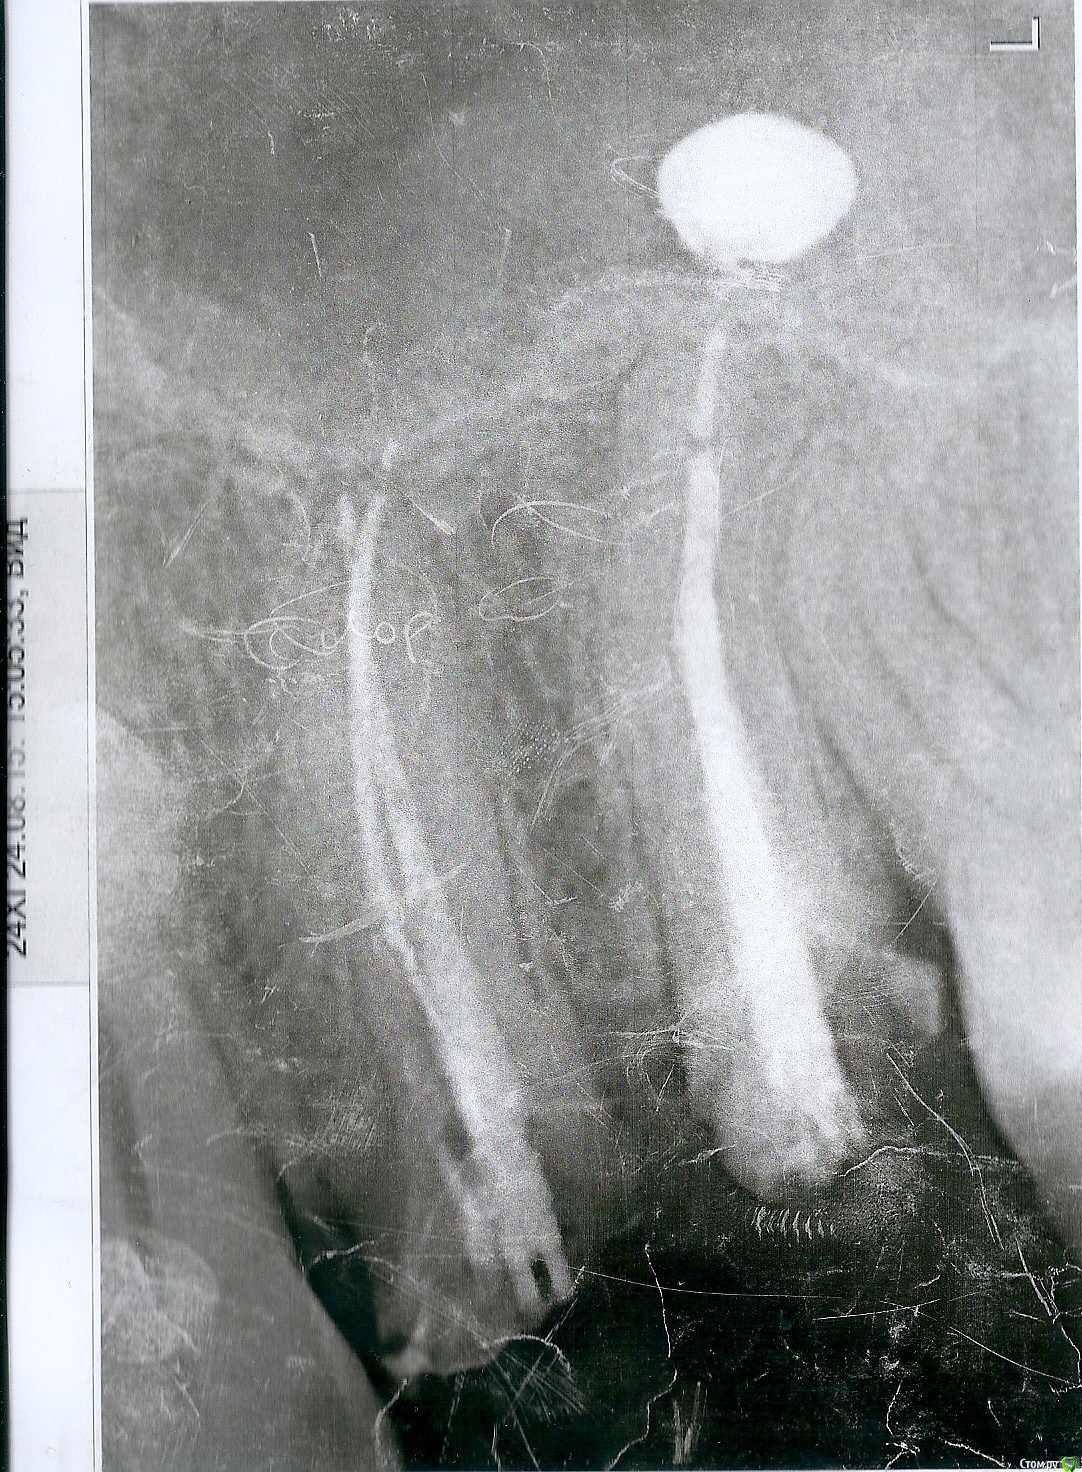

Пациентт Опубликовано 14 октября, 2015 Автор Поделиться Опубликовано 14 октября, 2015 что то вас беспокоит,кт делали? выкладывайте срезы.В этом и вопрос - стоит ли мне беспокоиться? Могут ли быть какие-то последствия для организма в целом и для гайморовой пазухи в частности? Если Метаплекс будет рассасываться долго или вообще не рассасется. И думаю, стоит ли идти к лору, чтобы его удалять.P.S.Прикладываю снимки. Ссылка на комментарий

red_butler Опубликовано 14 октября, 2015 Поделиться Опубликовано 14 октября, 2015 за 2 месяца он не рассосался. когда сделан выложенный снимок? 1 Ссылка на комментарий

Brigita Опубликовано 14 октября, 2015 Поделиться Опубликовано 14 октября, 2015 по снимку необъективо оценивать наличие пасты в пазухе. Нужно кт. 1 Ссылка на комментарий

Пациентт Опубликовано 14 октября, 2015 Автор Поделиться Опубликовано 14 октября, 2015 когда сделан выложенный снимок? Снимок был сделан 1,5 месяца назад. Неделю назад делали другой снимок, картина почти такая же. Ссылка на комментарий

St. Опубликовано 15 октября, 2015 Поделиться Опубликовано 15 октября, 2015 КТ позволит максимально объективно оценить объем и положение выведенного материала. 1 Ссылка на комментарий